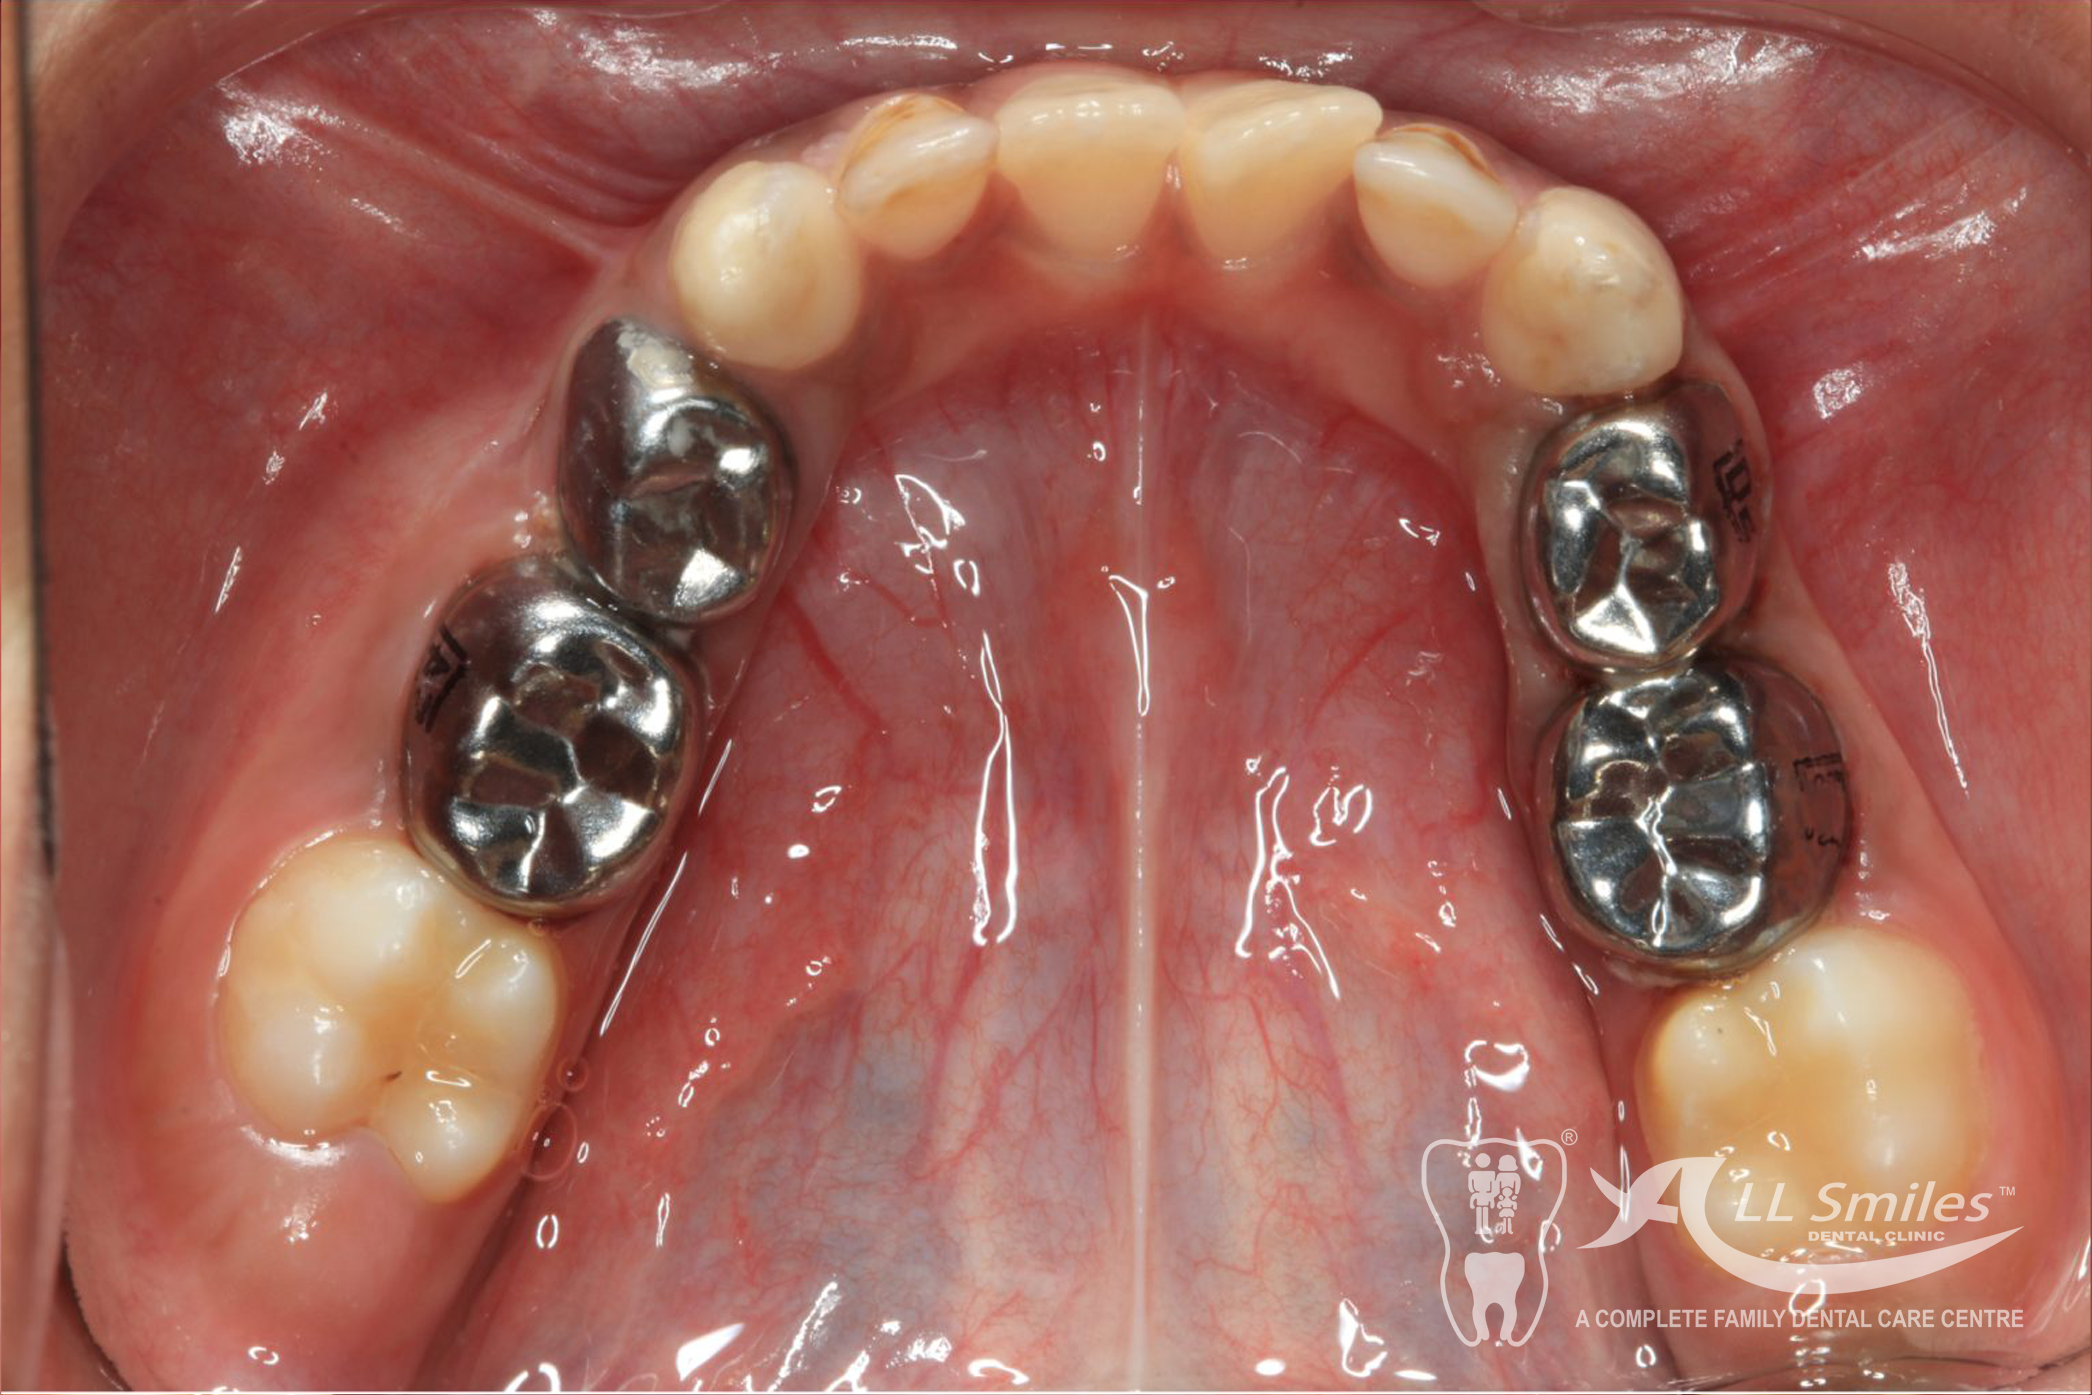

Crowns are tooth-shaped caps that cover and protect damaged or weakened teeth. They are commonly used for baby teeth that have extensive decay or are at risk of fracture.